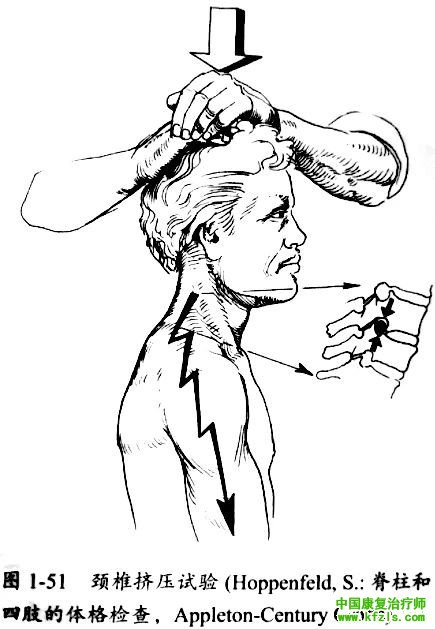

>>颈椎挤压试验

颈椎挤压试验阳性为颈椎被动向下挤压时疼痛增加。该试验的目的是使椎间孔变窄、 小关节压力增加或肌肉痉挛,从而加重对颈神经根的刺激,出现疼痛或放射痛。该试验可准确诱发上肢疼痛,有助于定位病变节段。

检査方法:患者取坐位或卧位,检査者双手手指相扣,以手掌面压患者头顶,观察颈椎或上肢疼痛是否加剧,并注意疼病的具体分布是否与先前描述的节段一致(图1-51 )。